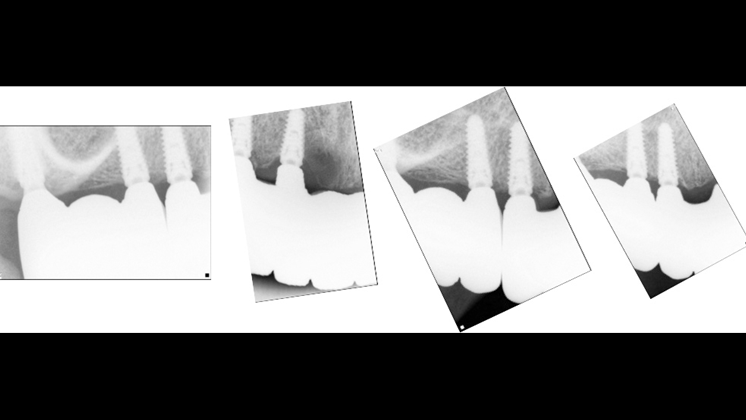

“AnyRidge shows excellent initial stability

& stable results after immediate loading in

upper fully edentulous case. ”

Clinical case: Extraction of all teeth in upper maxilla,

immediate implant placement, & provisionalization

- Courtesy of Dr. Iulian Filipov, Romania -

Keywords

AnyRidge, immediate placement, immediate provisionalization, maxillary fully edentulous case, initial stability, edentulous, Dr. Iulian Filipov, R2GATE, MEGA ISQ

Products:

AnyRidge implant system, Mega ISQ, R2GATE